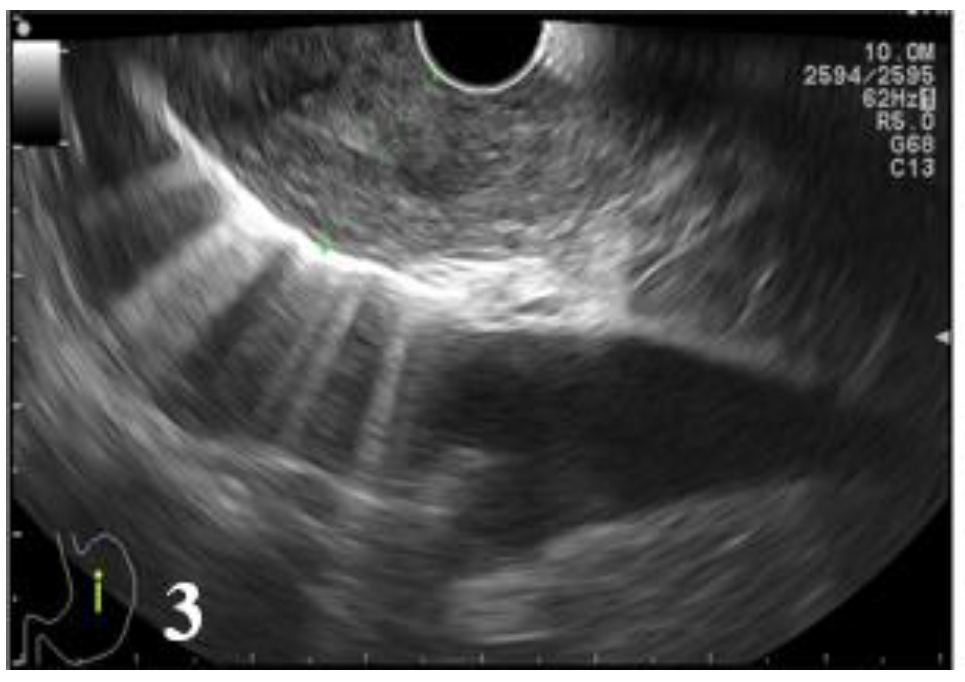

Therefore, of 19 cases of histologically diagnosed tumors as T3, 7 cases were incorrectly diagnosed: 4 cases were under-staged as T2 (21.05%) and 3 cases over-staged as T4 (15.79%). In case of T4 tumors, endoscopic ultrasound correctly diagnosed 3 cases, while in 3 cases endoscopic ultrasound erroneously considered T3 tumors as T4. A T4 tumor case was under-staged (25%) (Figure 3 and Figure 4, Table 10).

Figure 3.

EUS image showing the lesion that involves all the layers of the distal esophageal wall without invasion into the aorta (T3).